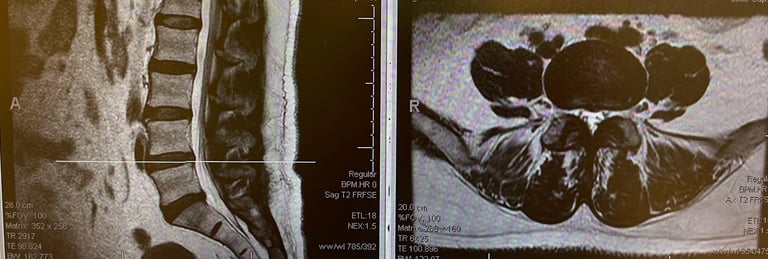

Focused on lumbar spine imaging excellence.

Spine Imaging

Precision in anterior and oblique views.